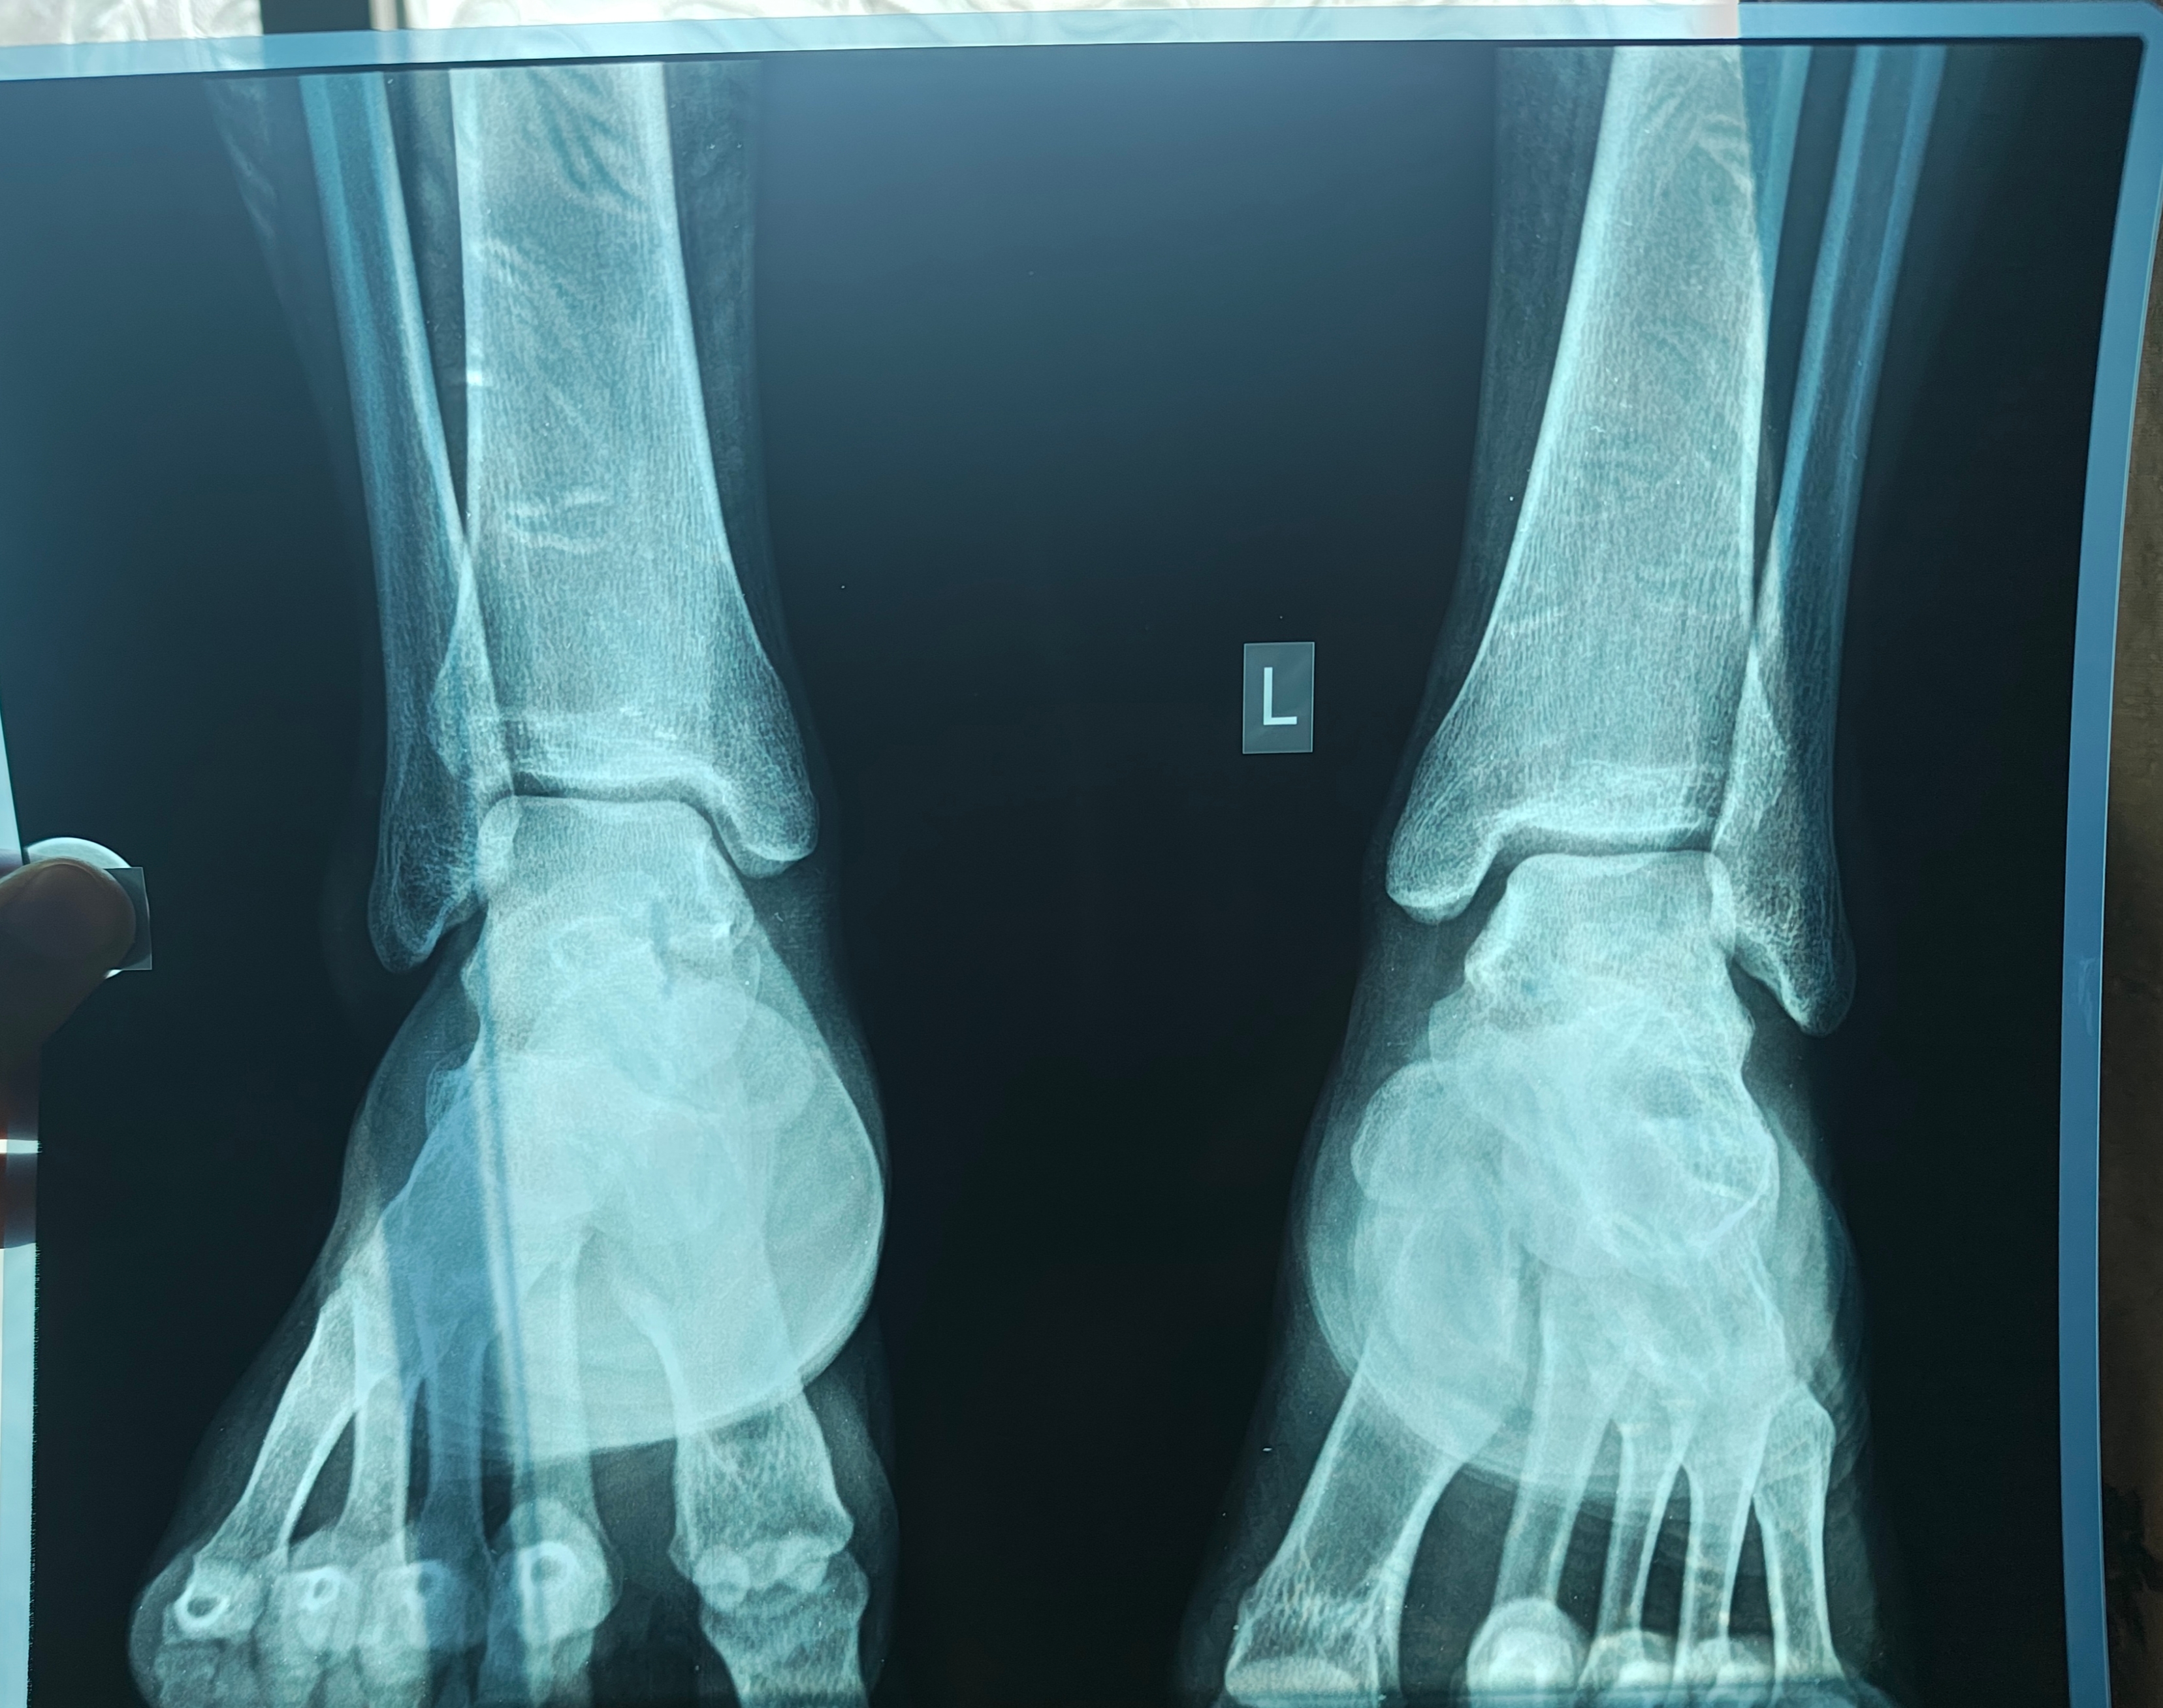

so i thought id still have my growth plates open and took an xray of my ankles and wrists as suggested by my doctor, to check the growth plates.

ran it through grok ai and chatgpt and they are saying the growth plates are open and there's room for heightmaxxing, but idk, yet to talk to my doctor about it, will update.

please have a look and lemme know if they're still open or not, and if open what's the best way to HeightMaxx, im ready to take peptides supplements and whatever, just not the limb lengthening surgery.